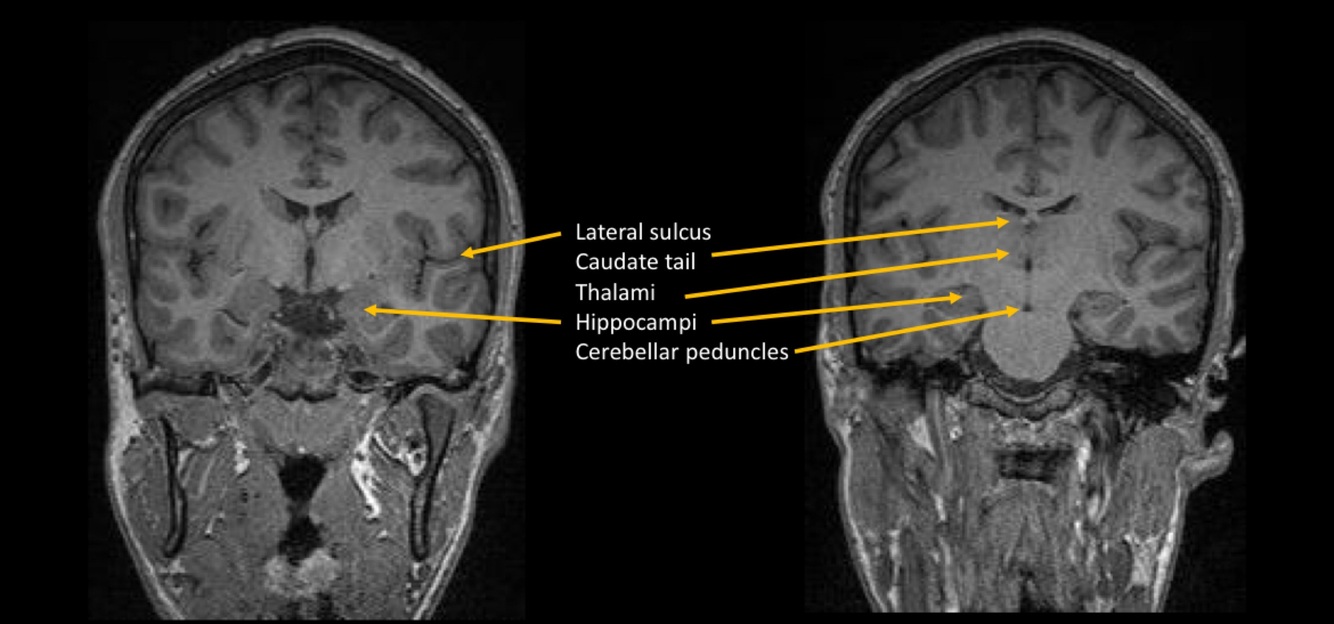

Name the structure

Hypophisis